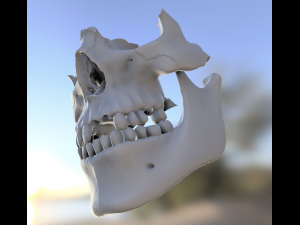

dental anatomy library with thimble crowns - azure Model do druku 3D

dental anatomy library with thimble crowns - azure. position of thimble crowns is same as teeth position. all teeth is separate files. if you want to publish or sell these files please contact me.

dental anatomy teeth tooth morphology jaw skelet exocad cad 3dprint library dentist science medicine mouth toothbrush body printable thimble crownBrak komentarzy dla tego produktu.